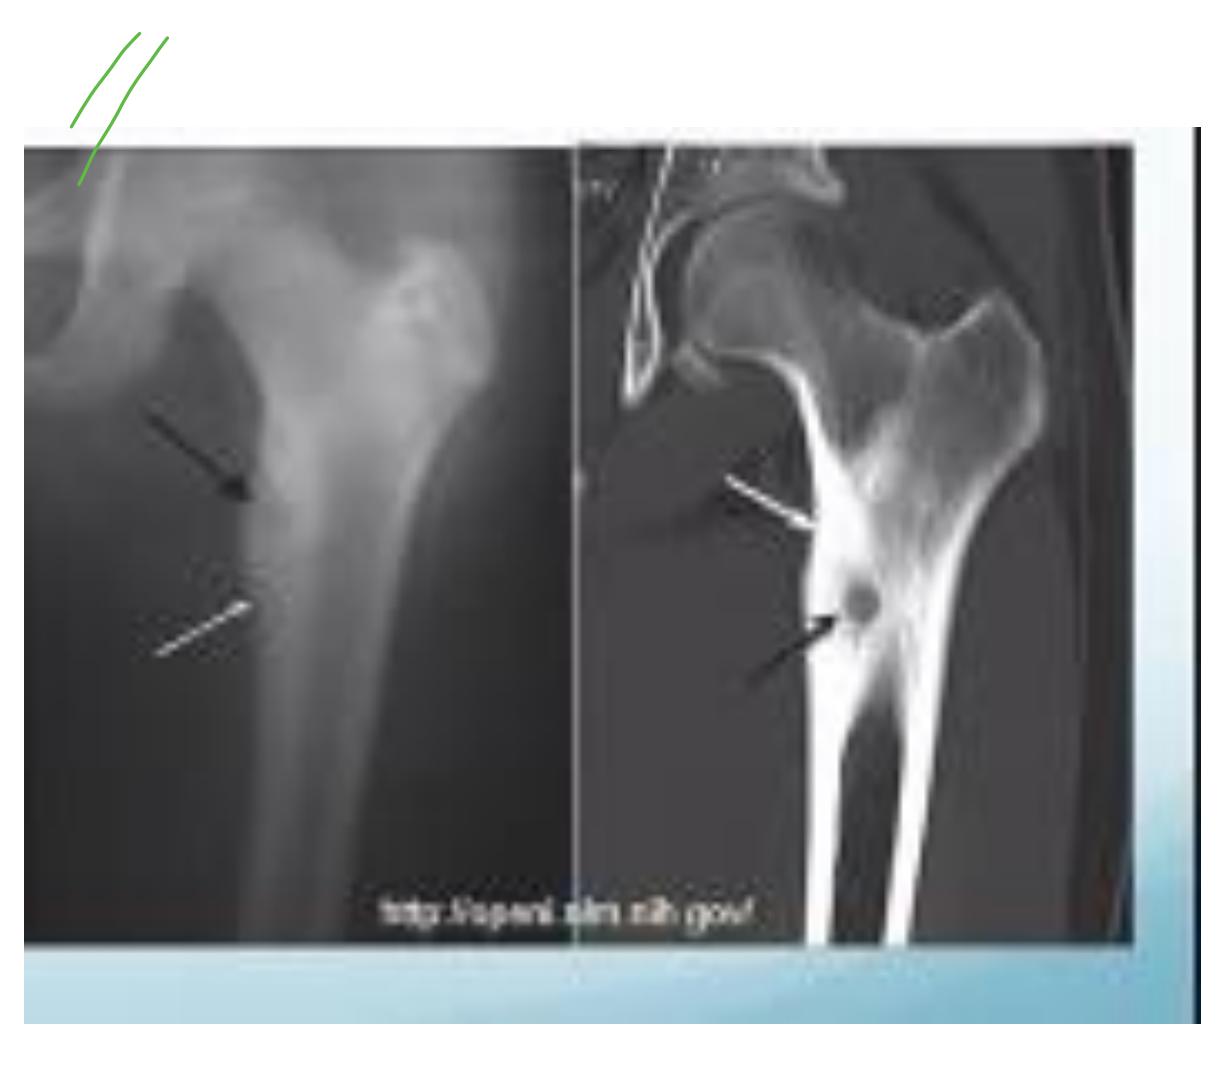

Osteosarcoma

Typical Presentation:

- Age: 10-20 years

- Pain and mass

- Location: Metaphysis of long bone

Characteristic Radiological Findings:

- Sunburst (Sunray) appearance

- Codmanโs triangle

- Periosteal reaction

- Bone eating appearance

Clinical Cases:

-

14-year-old patient with pain and swelling at lower right thigh

- Most important X-ray findings: Sun ray appearance, Codmanโs triangle

- Diagnosis: Osteosarcoma

14-year-old patient complaining of pain and swelling at lower R thigh

- Findings: Codmanโs triangle, Sun burst appearance